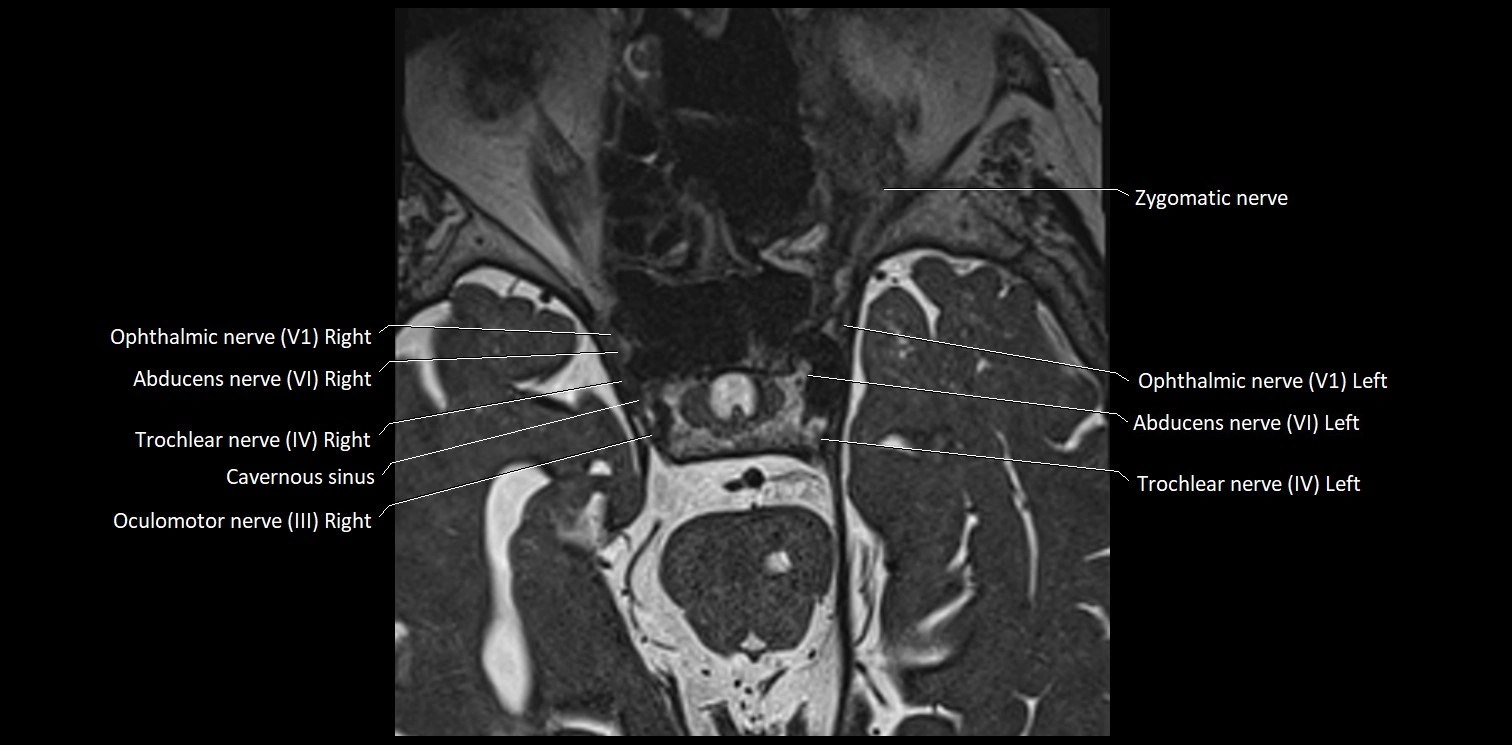

MRI Appearance

• The abducens nerve is a small, thin, linear structure

• Best visualized on high-resolution T2-weighted 3D MRI sequences (e.g., FIESTA or CISS)

• Seen as a hypointense (dark) line running from the brainstem at the pontomedullary junction, traversing the prepontine cistern, and entering Dorello’s canal under the petrosphenoidal ligament, then into the cavernous sinus, and finally the orbit

• May be challenging to visualize in standard MRI due to its small size

• Pathology may be inferred by absence, displacement, or enhancement of the nerve

MRI images

image